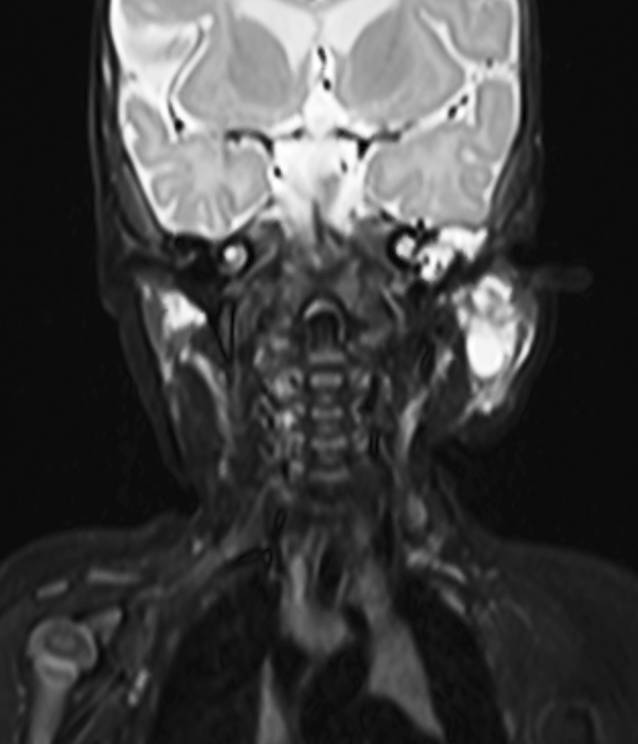

Abb. 6

Patientin 3. Im axialen T1-Magnetresonanztomogramm mit Kontrastmittel ist nahezu das gesamte Leberparenchym diffus von kleinzystischen Läsionen durch- und ersetzt

Fallbericht 3

Im Rahmen der 1. Mutter-Kind-Pass-Untersuchung fiel bei der Patientin ein ausladendes Abdomen auf (Tab. 1). Das Hautkolorit war blass, das Abdomen druckdolent, die Leber 3 Querfinger unter dem Rippenbogen tastbar. Die Herzfrequenz lag bei 150/min. Es fanden sich außerdem multiple kutane Hämangiome, jedoch durchwegs in einer Größe von ≤5 mm. In der MRT kamen multiple, die gesamte Leber durchsetzende hyperperfundierte Läsionen zur Darstellung (Abb. 6). Die initiale basale Thyreotropin(TSH)-Konzentration war auf 42,37 mU/l (Normwert: 0,45–10,0) erhöht, während die Konzentrationen an freiem Trijodthyronin (fT3) und freiem Thyroxin (fT4) normwertig waren. In der Echokardiografie fanden sich keine Zeichen einer kardialen Dekompensation. Es wurde umgehend eine perorale Therapie mit Prednisolon (2 mg/kg und Tag), Propranolol (Tag 1: 1 mg/kg und Tag, ab Tag 2: 2 mg/kg und Tag) und Levothyroxin (25 μg) begonnen; Prednisolon wurde 2 Wochen lang volldosiert verabreicht und anschließend über 1 Woche ausgeschlichen. Es erfolgten sonografische Kontrollen, anfangs in 2‑wöchigen, dann in 4‑ bzw. 6‑wöchigen Abständen, wobei rund 2 Monate nach Therapiebeginn die schlechtere Abgrenzbarkeit der Einzelherde für eine beginnende Rückbildung sprach. Die Propranololtherapie wurde in einer Dosis von täglich 1,5 mg/kg für 11 Monate fortgeführt und schließlich nach Dosisreduktion über 4 Wochen knapp ein Jahr nach Beginn beendet. In der MRT-Untersuchung konnten keine Läsionen mehr nachgewiesen werden. Levothyroxin wurde nach einer Therapiedauer von 2 Monaten abgesetzt. Die kutanen Hämangiome waren langsam regredient und bildeten sich ebenfalls vollständig zurück.